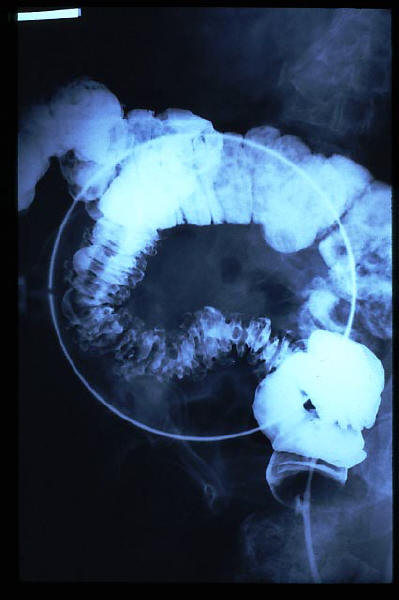

Diverticulosis de colon.

Diverticulosis de colon. Megacolon.